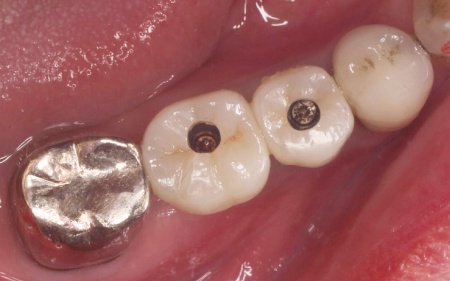

一定期間をおいてインプラントがあごの骨に定着したことを確認したあと、歯ぐきの上にインプラントの一部を出すための二次手術を行いました。

歯ぐきの治癒を待ってから型取りを行い、インプラントの上に装着する人工歯を作製・装着して治療を終了しています。